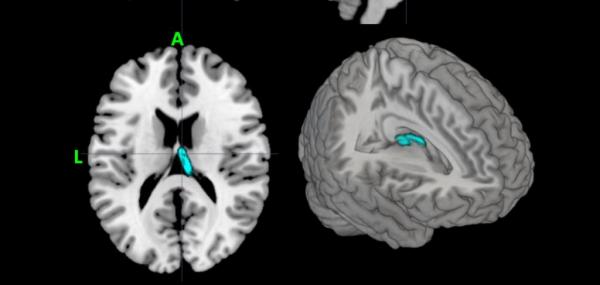

Αμερικανοί επιστήμονες ανέπτυξαν ένα νέο υπολογιστικό σύστημα που είναι ικανό να διαγνώσει τη μείζονα κατάθλιψη, σύμφωνα με στοιχεία που δημοσίευσαν στο επιστημονικό έντυπο Psychiatry Research - Neuroimaging.